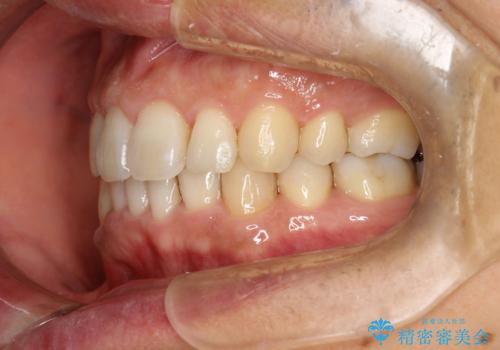

- 以前、上下左右4本抜いてワイヤー矯正をしていた方で、後戻りで下の前歯のガタガタを気にして来院されました。

マウスピース矯正にて、下の歯はIPR(歯と歯の間を削る)を入れることでガタガタの改善、咬み合わせの深さも改善をはかる治療計画をたてました。

歯と歯の間を削って隙間を作って矯正をしています。

保定装置(後戻り防止のための装置)は、基本的にはマウスピースタイプをお渡ししているのですが、患者様のご希望で取り外ししないタイプを希望されたので、前歯の裏側を細いワイヤーで固定(ボンディングリテーナー)を作成しています。